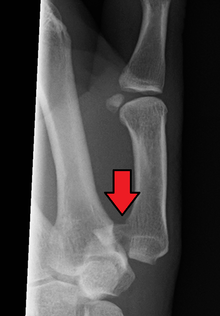

Bennett fracture is a fracture of the base of the first metacarpal bone which extends into the carpometacarpal (CMC) joint.[1] This intra-articular fracture is the most common type of fracture of the thumb, and is nearly always accompanied by some degree of subluxation or frank dislocation of the carpometacarpal joint.

Though these fractures commonly appear quite subtle or even inconsequential on radiographs, they can result in severe long-term dysfunction of the hand if left untreated. In his original description of this type of fracture in 1882, Bennett stressed the need for early diagnosis and treatment in order to prevent loss of function of the thumb CMC joint, which is critical to the overall function of the hand.[3]